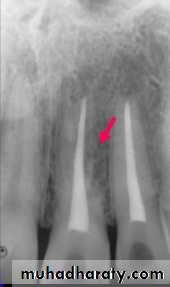

Inflammatory Resorption-Resorption of cementum and dentin

-Inflammatory reaction in the periodontal

ligament

Etiology

Infamatory resorption

-Surface resorption of cementum

exposing dental tubuless

Infamatory resorption-Surface resorption of cementum

-Pulp necrosis

Infamatory resorptionSurface resorption of cementum

exposing dental tubules

Pulp necrosis

Toxic products from the pulp provoke

an inflammatory response in the PDL